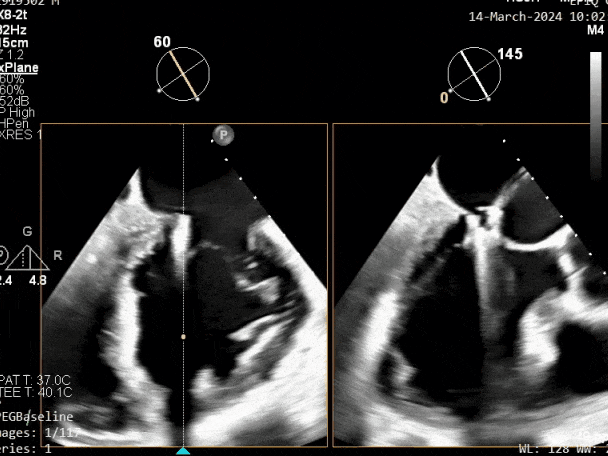

超声心动图:

二尖瓣后叶活动受限,呈房源性栓系,以P3区为重,二尖瓣前叶假性脱垂,二尖瓣瓣环前后径49mm,左右径40mm。

PISA法测r=12mm,EROA=0.72cm2,RVOL=100ml,RF 26%。LVEDD 57mm,左房71*59*77mm,右房55*69mm,LVEF 70%。

超声提示:

二尖瓣反流(重度,4+级,Carpentier I型)

三尖瓣反流(轻度)

主动脉瓣反流(轻度)

双房及心耳内未见确切血栓回声

2. 本例患者外院超声心动图考虑二尖瓣前叶脱垂,入院后经食道超声心动图明确该患者为二尖瓣后叶活动受限,呈房源性栓系,二尖瓣前叶假性脱垂,超声特征表现为心房功能性二尖瓣反流终末期,呈现出很典型的二尖瓣后瓣环向左室游离壁顶部位移和后叶挛缩表现,同时合并有明显的二尖瓣瓣环扩张、圆形化,左房增大等不利因素,术中通过精准的影像指导和手术操作,成功行TEER,二尖瓣反流程度减轻至微量。